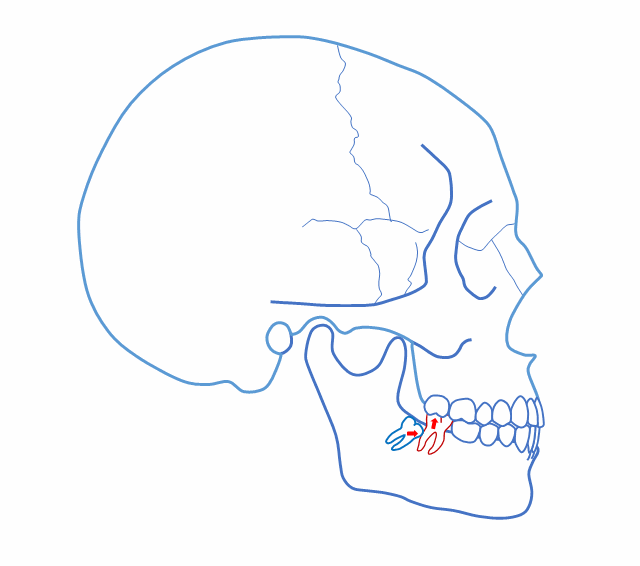

第一,“建立了咬合關(guān)系”可以不拔?

正位萌出到位,在牙尖交錯(cuò)位建立咬合關(guān)系,只是一個(gè)靜態(tài)的狀況??陬M系統(tǒng)的功能要靠運(yùn)動(dòng)來(lái)實(shí)現(xiàn),而一旦動(dòng)起來(lái),很多“看”似建立了正常咬合關(guān)系的智齒很可能會(huì)造成咬合干擾,給整個(gè)口頜系統(tǒng)帶來(lái)傷害。

這樣 “萌出到位有咬合” 的智齒應(yīng)該 拔掉